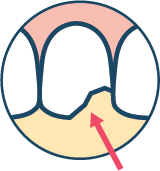

CAUSE: Gums often recede as a result of a few factors: aggressive brushing, gum disease (periodontitis), aging or dry mouth for prolonged periods of time. The receding gums expose the softer tissue of the teeth known as dentin. Dentin is far more susceptible to changes in hot and cold temperatures.